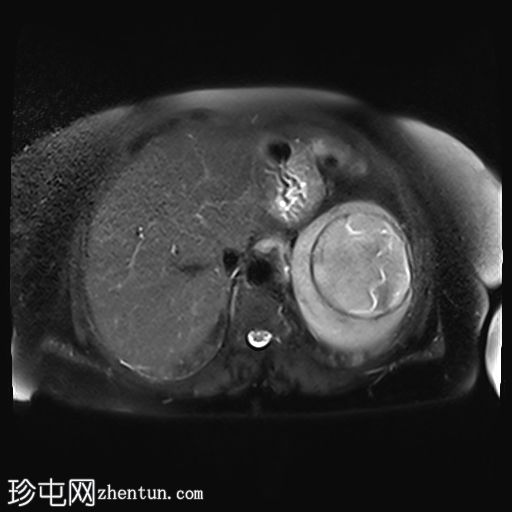

MRI

5.jpg

轴位

T2加权像

脾脏内可见一边界清晰的病变,T2加权像呈中等信号强度,边缘低信号提示钙化。病变内可见漂浮膜,呈棘球蚴囊肿特征性的蛇形征。

胆结石。